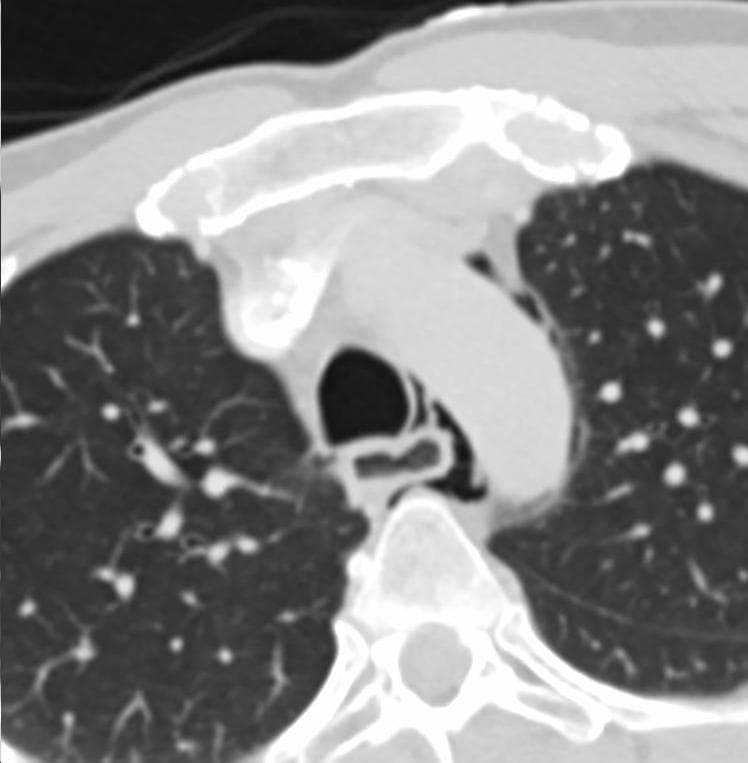

Esophageal rupture is a rupture of the esophageal wall. Iatrogenic causes account for approximately 56% of esophageal perforations, usually due to medical instrumentation such as an endoscopy or paraesophageal surgery. In contrast, the term Boerhaave syndrome is reserved for the 10% of esophageal perforations which occur due to vomiting. Spontaneous perforation of the esophagus most commonly results from a full-thickness tear in the esophageal wall due to a sudden increase in intraesophageal pressure combined with relatively negative intrathoracic pressure caused by straining or vomiting (effort rupture of the esophagus or Boerhaave's syndrome). Other causes of spontaneous perforation include caustic ingestion, pill esophagitis, Barrett's esophagus, infectious ulcers in patients with AIDS, and following dilation of esophageal strictures. In most cases of Boerhaave's syndrome, the tear occurs at the left postero-lateral aspect of the distal esophagus and extends for several centimeters. The condition is associated with high morbidity and mortality and is fatal without treatment. The occasionally nonspecific nature of the symptoms may contribute to a delay in diagnosis and a poor outcome. Spontaneous effort rupture of the cervical esophagus, leading to localized cervical perforation, may be more common than previously recognized and has a generally benign course. Preexisting esophageal disease is not a prerequisite for esophageal perforation but it contributes to increased mortality. This condition was first documented by the 18th-century physician Herman Boerhaave, after whom it is named. A related condition is Mallory-Weiss syndrome which is only a mucosal tear. In case of iatrogenic perforation common site is cervical esophagus just above the upper sphincter whereas spontaneous rupture as seen in Boerhaave's syndrome perforation commonly occurs in the lower one-third of esophagus. The classic history of esophageal rupture is one of severe retching and vomiting followed by excruciating retrosternal chest and upper abdominal pain.